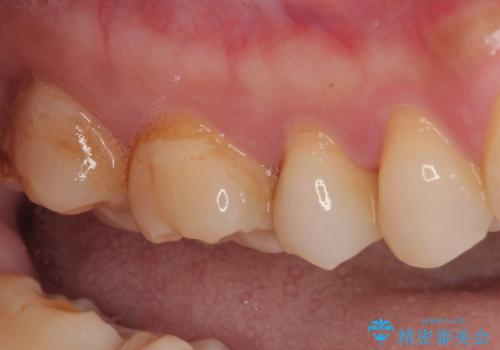

- むし歯と銀歯を気にして来院された患者様です。

銀歯の歯は既に根管治療がされており、根尖部に病変が認められないため、根管治療を行うことなくオールセラミッククラウンにて補綴治療を行うこととしました。

むし歯の症状のある歯は、ややしみることがある程度でしたが、レントゲン写真では非常にむし歯が大きく、神経組織に迫っている状態でした。

術前診査では神経を全て取る可能性は低いと予想されましたが、一部切除する可能性があることを伝えた上で治療を行うこととしました。